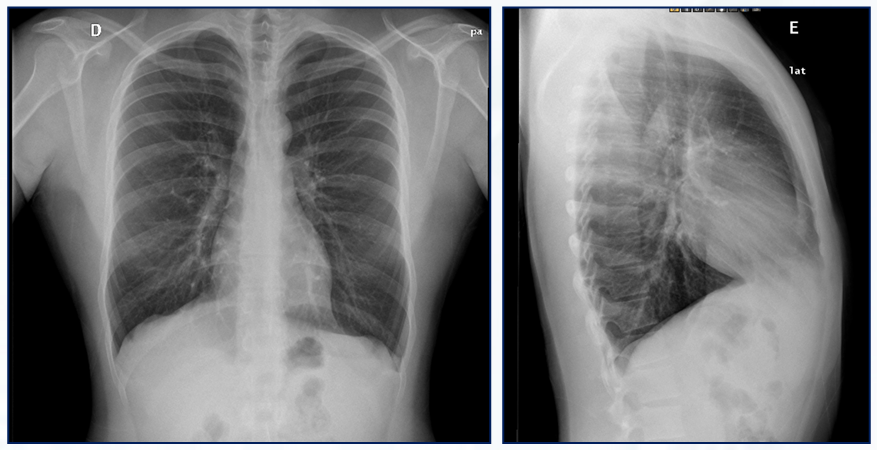

Qual o achado dessa Rx de tórax PA?

Hiperinsuflação pulmonar nos segmentos inferiores dos pulmões em paciente com deficiência de alfa-1-antitripsina.

Achados são semelhantes aos da DPOC, no entanto, restritos às regiões pulmonares inferiores.